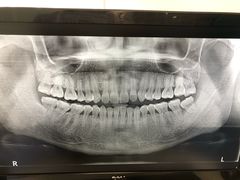

• 马泷齿科·皓康门诊(尚都SOHO店)

• -马泷齿科·皓康门诊(尚都SOHO店)